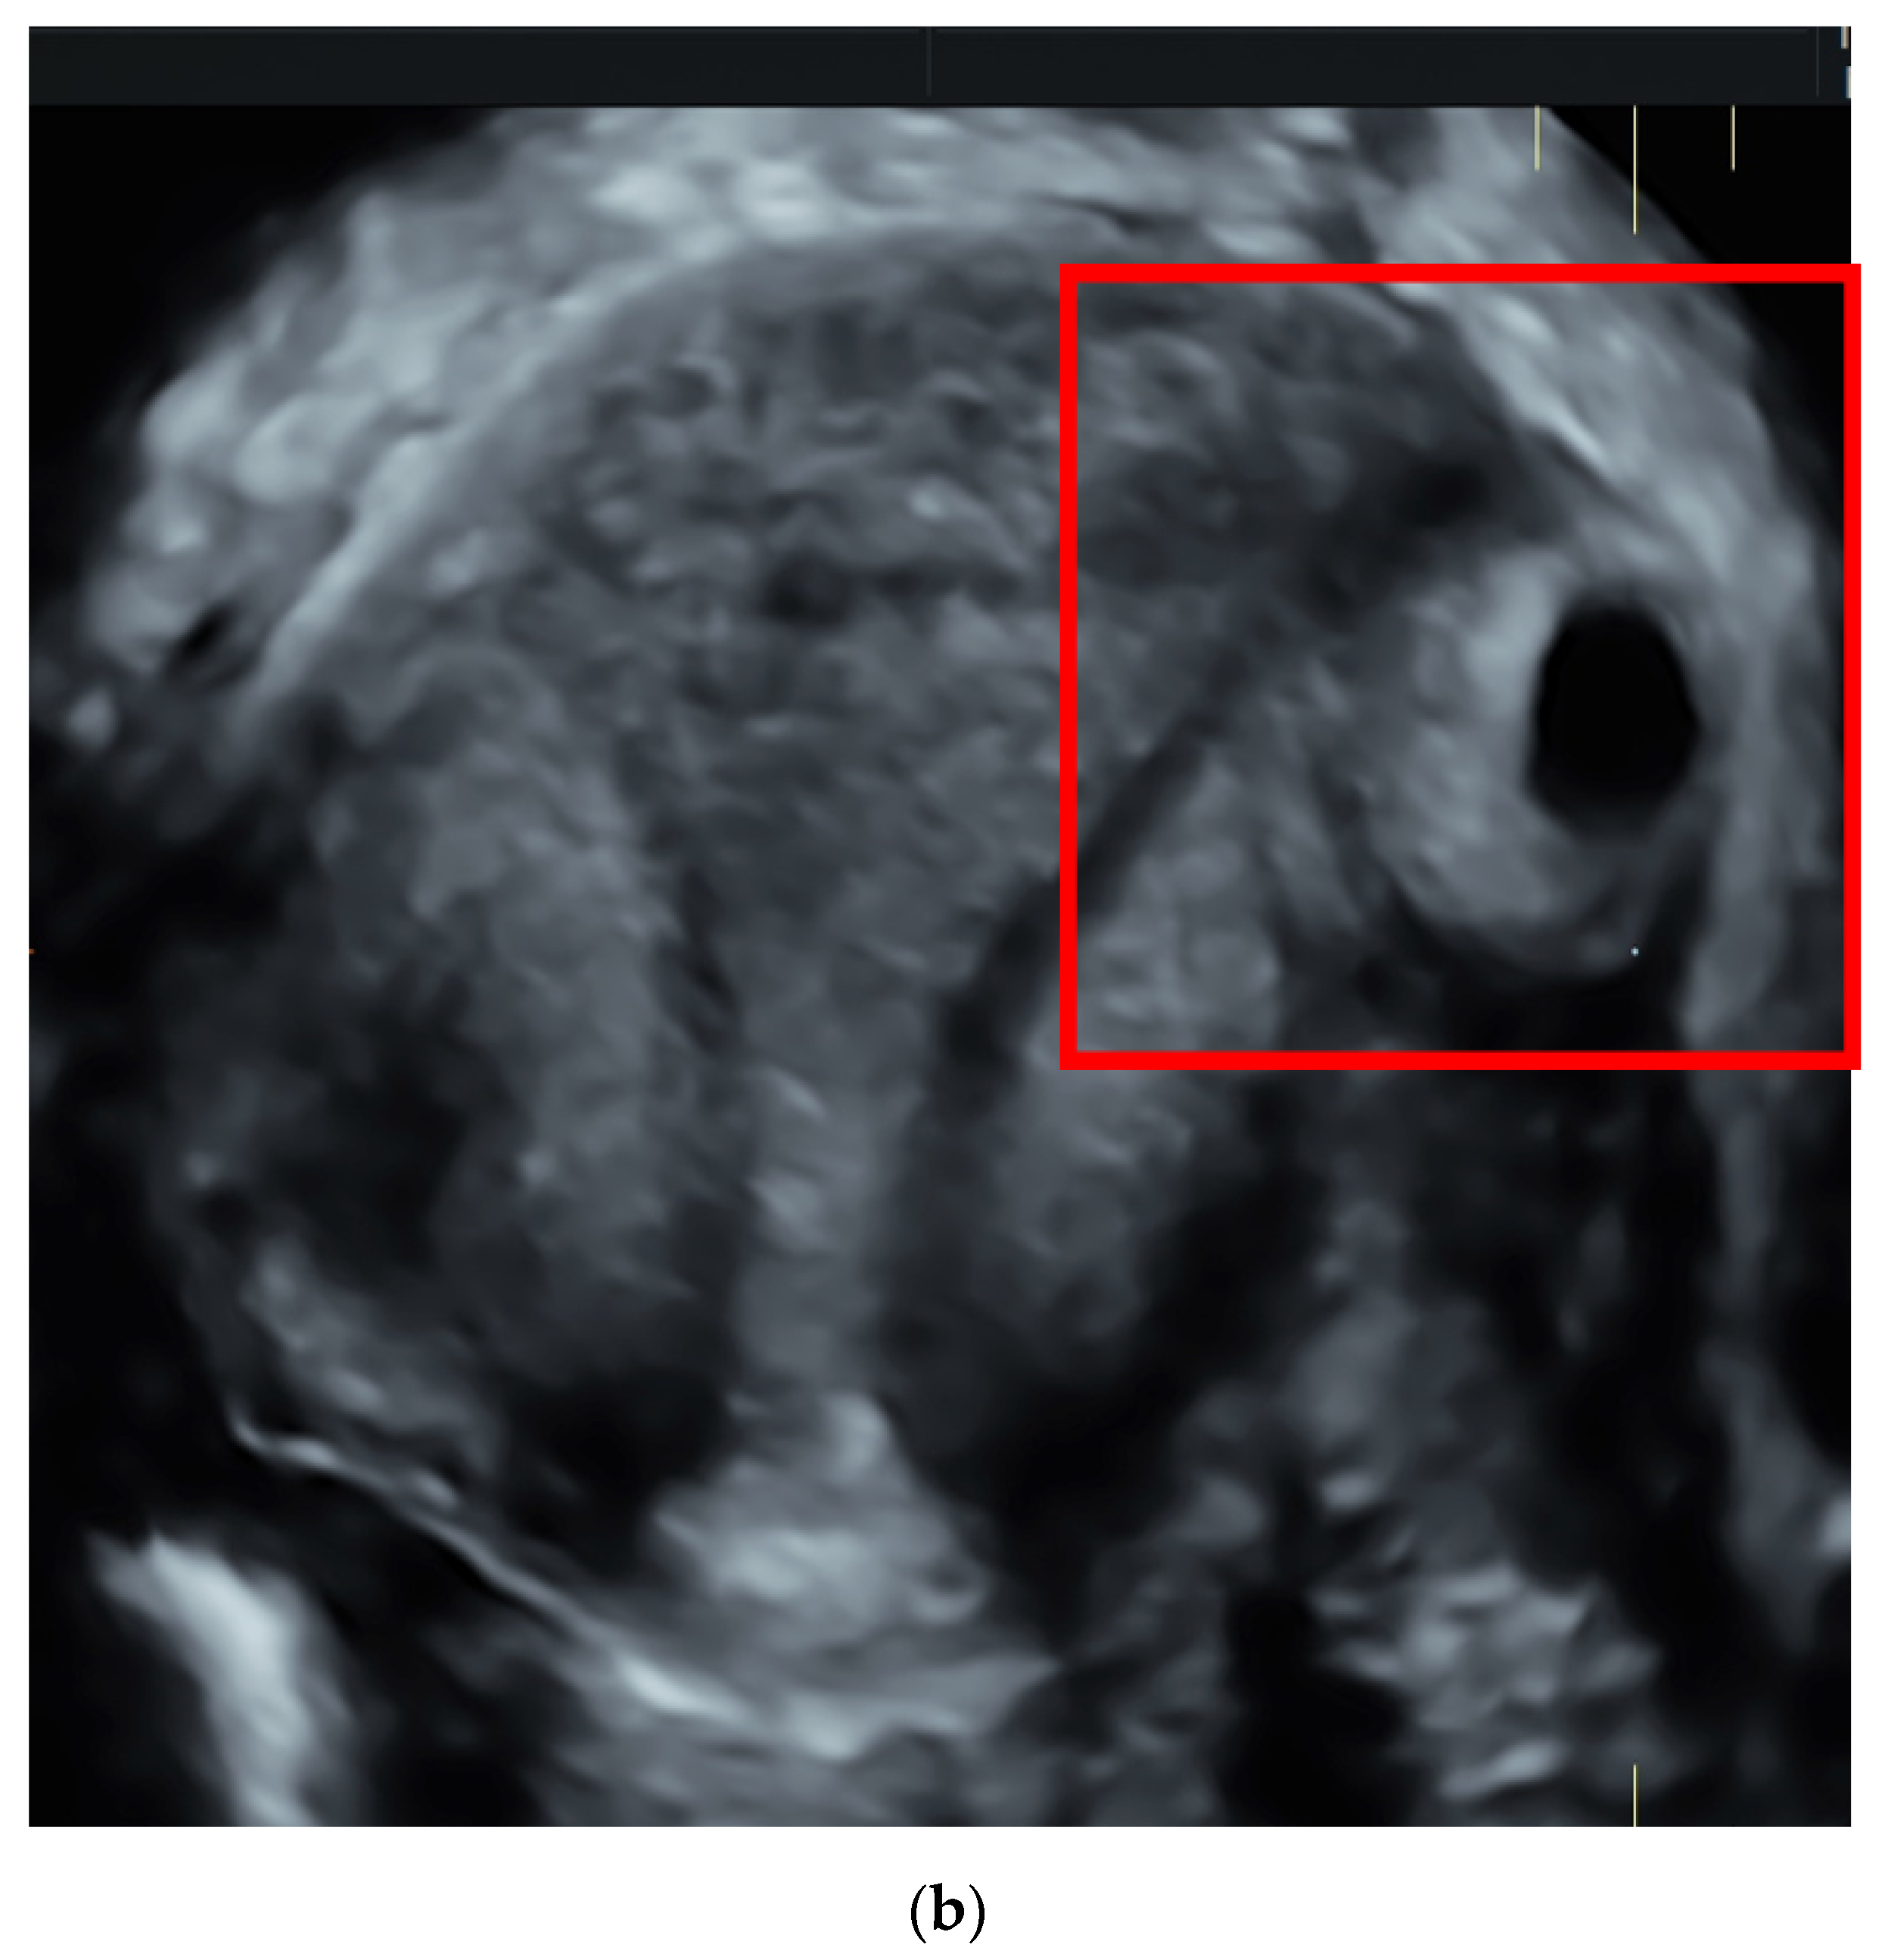

| Current Case | G2P0 (1 Previous EP treated by LPS: monolateral salpingectomy) | 7 weeks | 9 | + | 22,272 | Mifepristone 600 mg + MTX 1 mg/kg + 0. 1 mg folinic acid (four doses) |